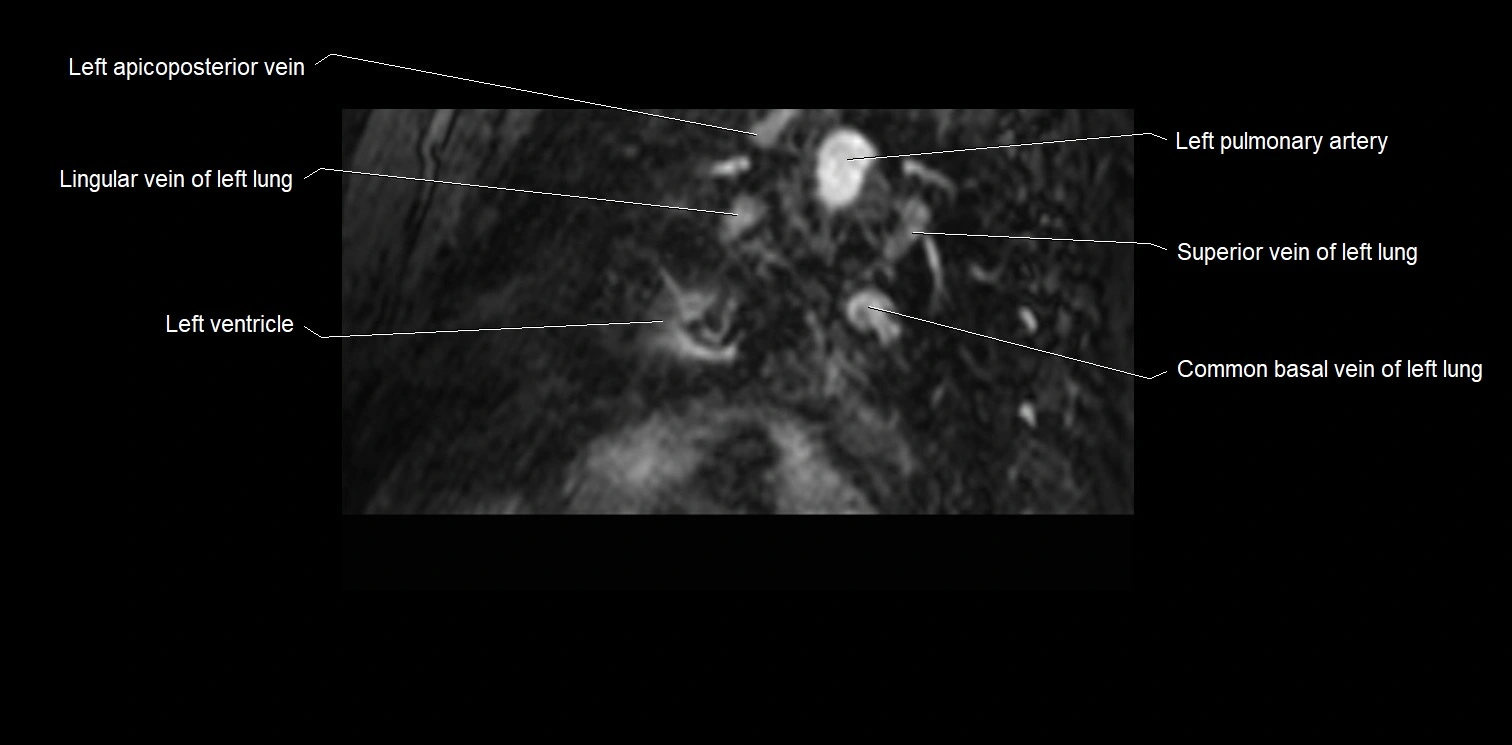

- Left pulmonary artery

- Lingular vein of left lung

- Left ventricle

- Superior vein of left lung